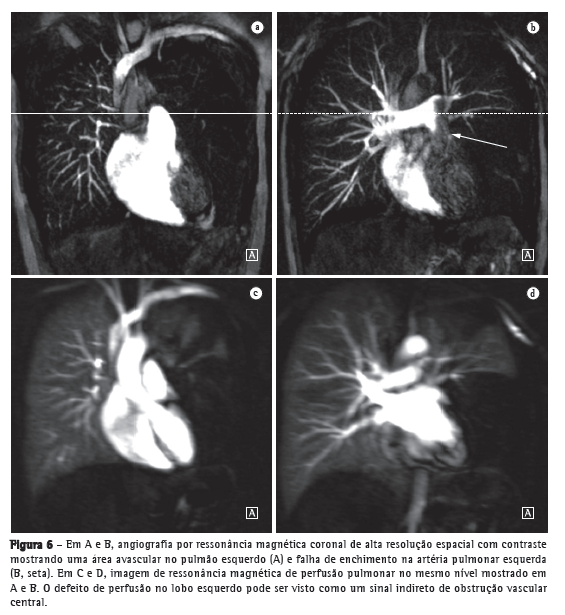

Avanços técnicos substanciais em angio-RM pulmonar foram introduzidos nos últimos anos (Figuras 5 e 6). Novas melhorias estão em andamento; dentre elas, o uso de imagens paralelas, compartilhamento de visão, angiografia do tipo time-resolved echo-shared(17-19) e perfusão pulmonar. Essas técnicas encurtaram o tempo de aquisição da angio-RM, tornaram-na menos suscetível a artefatos de movimento e melhoraram a resolução espacial. Um estudo mostrou que um protocolo combinado de RM (progressão de RM em tempo real para RM de perfusão, e desta para angio-RM) é confiável e sensível, produzindo resultados semelhantes aos obtidos com TC com multidetectores de 16 fileiras.(18)

O uso da RM permite uma avaliação abrangente da hipertensão pulmonar, sendo que a angio-RM e sequências de perfusão permitem a identificação e diferenciação de embolia pulmonar e outras entidades.(22,23) Além disso, a angio-RM permite uma avaliação detalhada da localização do material tromboembólico e, para o planejamento cirúrgico, a angio-RM é tão útil quanto a angiografia por subtração digital e a angiografia por TC.(24,25) Na RM, as sequências de perfusão podem ser avaliadas quantitativamente, o que permite que a gravidade da doença de pequenos vasos seja avaliada. A redução da perfusão correlaciona-se com a gravidade da doença, e resultados preliminares sugerem que a perfusão é um substituto sensível para o monitoramento da doença.(4) Imagens estruturais do pulmão permitirão a exclusão de doenças do parênquima pulmonar. Medidas de fluxo sanguíneo e pressão cardíaca direita permitem que se estimem a pressão arterial pulmonar e o esforço cardíaco e facilitam a identificação de doença valvular concomitante.